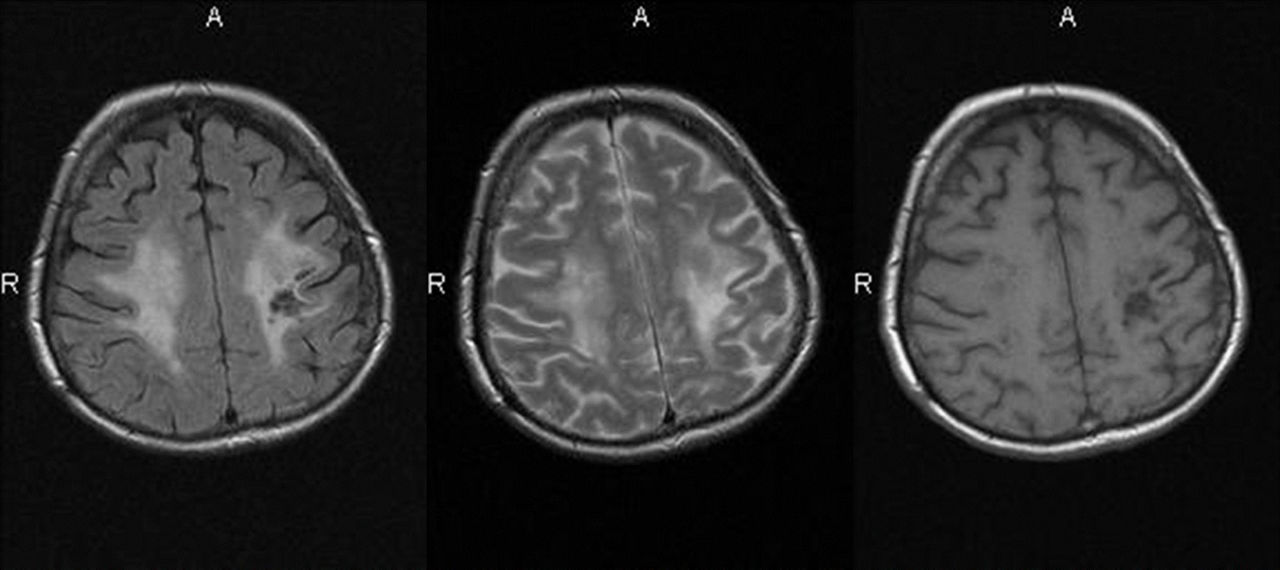

Abb.1: Periventrikuläre Läsionen in T2

Abb.2: T1+KM

Abb.3: PD

Herd im cervikalen Myelon: kurzstreckig, ungefähr 1 cm groß

Abb.4: T1 + KM